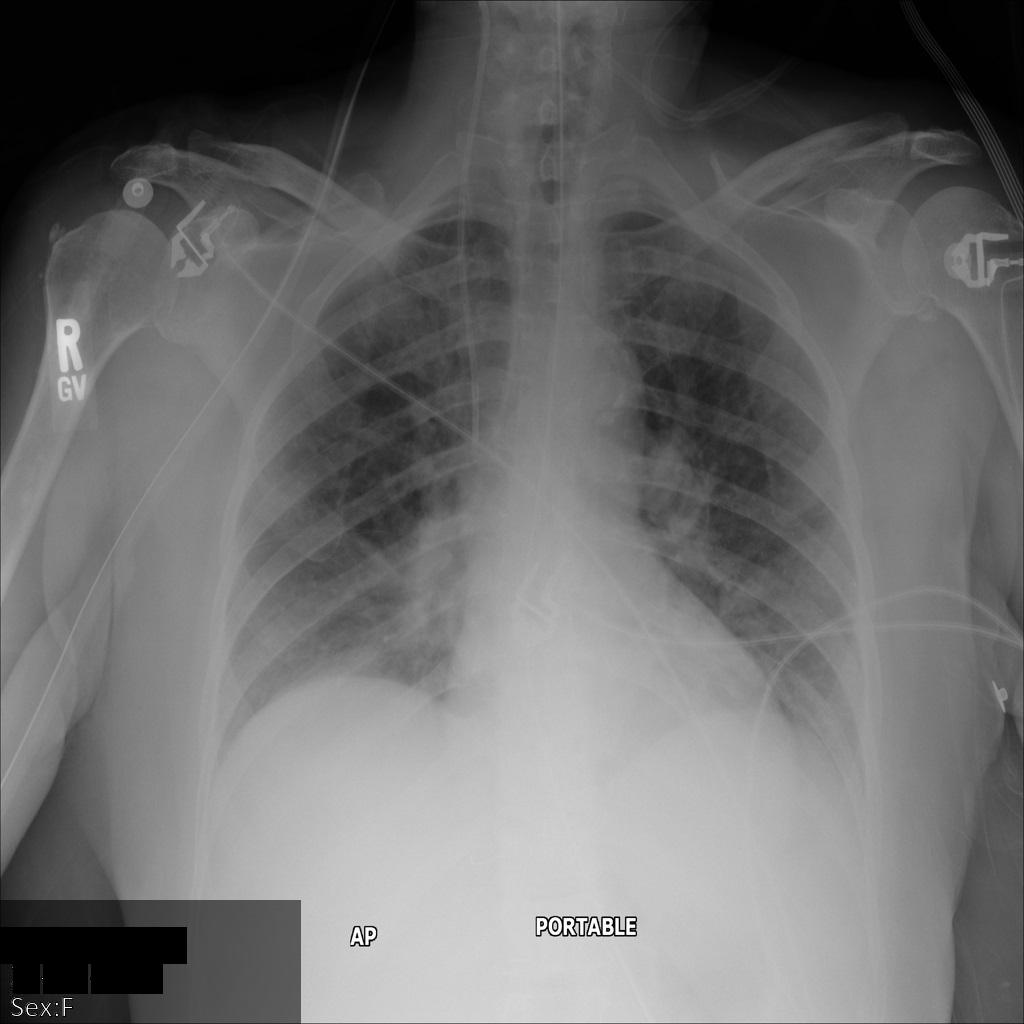

Después de enviar la imagen a la API de Cloud Healthcare, la imagen aparece de la siguiente manera. De las etiquetas proporcionadas en la removelist, solo se quita PatientBirthDate en la imagen, ya que es la única etiqueta de la lista de eliminación que corresponde a los metadatos visibles en la imagen.

Si bien PatientBirthDate en la esquina superior de la imagen se ocultó de acuerdo con la configuración de la removelist, la PHI de efecto quemado que se encuentra en la parte inferior de la imagen permanece. Para quitar también el texto quemado, consulta Cómo ocultar el texto quemado de las imágenes.